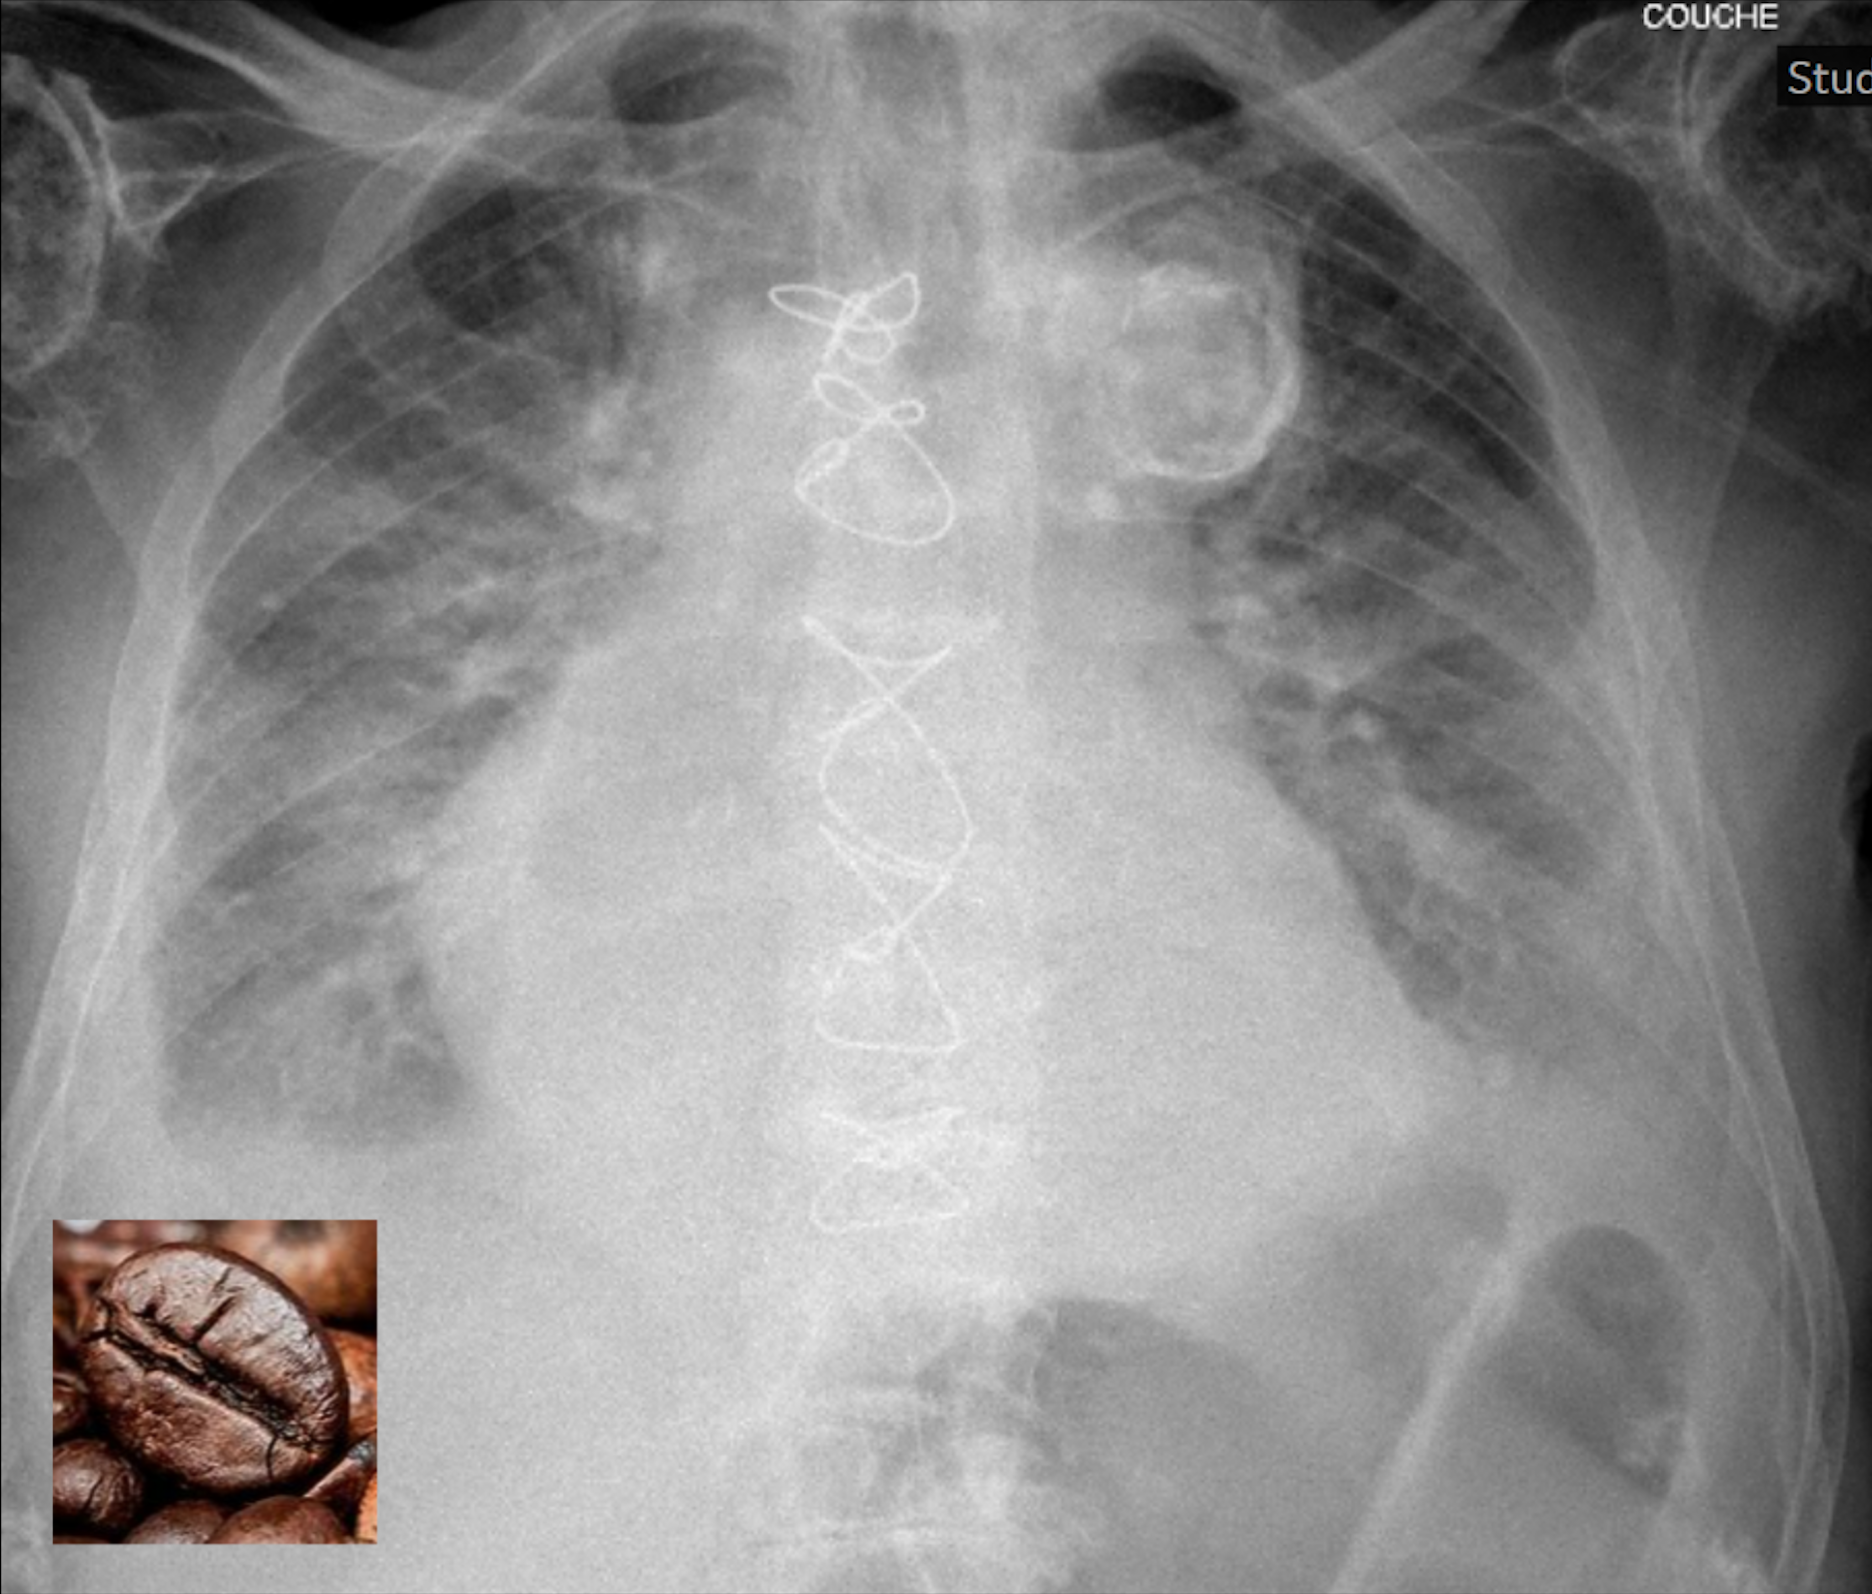

Le Coffee bean sign

Un patient de 94 ans, connu pour une cardiopathie ischémique, est amené aux urgences de l’EMS pour une dyspnée et une orthopnée. Le patient, qui a des troubles neurocognitifs, n’a pas de plaintes spontanée mais il est visiblement inconfortable, agité et dyspnéique. Au status, il est tachypnéique, nécessite 2L d’oxygène aux lunettes mais normocarde et normotendu. L’auscultation pulmonaire révèle des râles crépitants fins jusqu’à mi-plage. Les bruits abdominaux sont diminués en fréquence, l’abdomen est pléthorique et sa palpation diffusément sensible.

Un radiographie du thorax est effectuée. Tu fais ton ABCDE radiographique et trouves rapidement une explication à la clinique respiratoire : la cardiomégalie, l’œdème interstitiel et les épanchements pleuraux. Facile ! En complétant le E, tu constates une image ressemblant à un coffee bean sign.

Le coffee bean sign (signe du grain de café) est révélateur d’une torsion du sigmoïde autour de l’axe mésentérique, donc d’un volvulus sigmoïde et généralement visibile sur un ASP ou une Rx du thorax. Au vu des la mortalité élevée, il s’agit d’une urgence diagnostique et thérapeutique. Le traitement consiste en une coloscopie d’exsufflation pour dé-volvuler le sigmoïde qui s’est enroulé autour se son méso. En cas d’échec ou de complications telles qu’une souffrance digestive ou perforation, il s’gira d’effectuer une intervention chirurgicale.  La théorie sur le volvulus sigmoïde est décrite plus en détail dans l’image commentée « le Whirlpool sign », publiée il y a quelques mois sur les Bruits du déchoc (12 octobre 2023).  Un nouvel appel à l’équipe soignante de l’EMS confirme l’absence de selles depuis 48 heures, et deux épisodes de vomissement quelques heures avant la consultation. Le CT abdominal ne révèle finalement pas de volvulus sigmoïde, mais un iléus grêle d’allure paralytique, sans saut de calibre et sans signe de souffrance motivant une prise en charge conservatrice.